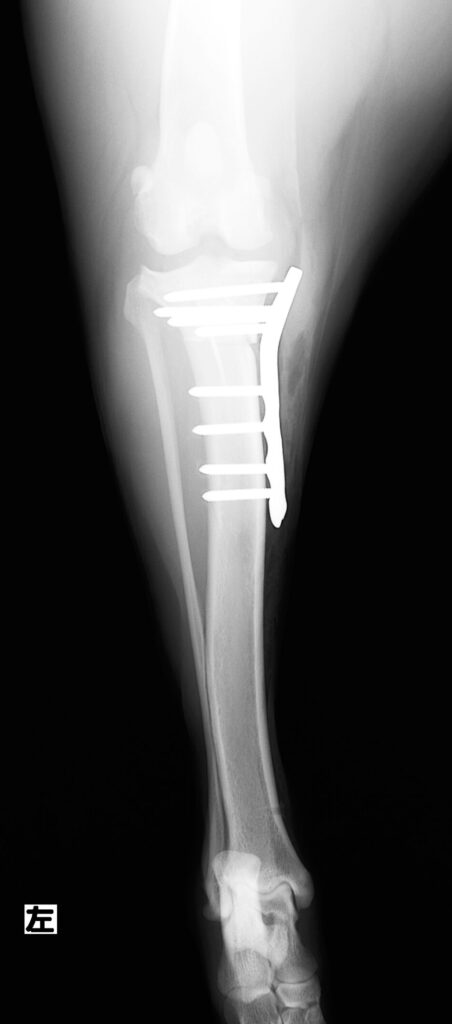

左後ろ足の膝から足根(足首)のレントゲン写真です。

体重を支えられない答えはこの画像に表れています。膝の脛(スネ)の骨が前方にせり出しています。

TPLO手術後の写真です。骨を切り回転させ、TPLOプレートと8本のスクリューで固定しました。

手術前と違い脛骨が後方に位置しています。